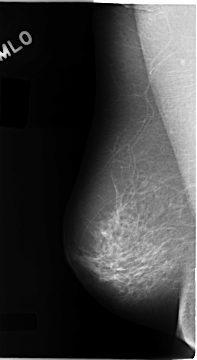

C_0108_1.RIGHT_MLO

RIGHT_CC LINES 4696 PIXELS_PER_LINE 2656 BITS_PER_PIXEL 12 RESOLUTION 50 NON_OVERLAY

RIGHT_MLO LINES 4672 PIXELS_PER_LINE 2560 BITS_PER_PIXEL 12 RESOLUTION 50 NON_OVERLAY